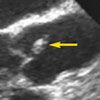

A 37-year-old man was brought to the emergency department (ED) after he had 2 near-syncopal events. The first occurred in the morning and rapidly resolved; the second occurred later in the day at work. The night before he had a headache and neck pain. In the ED, he reported left arm and leg weakness and was noted to have left facial droop.